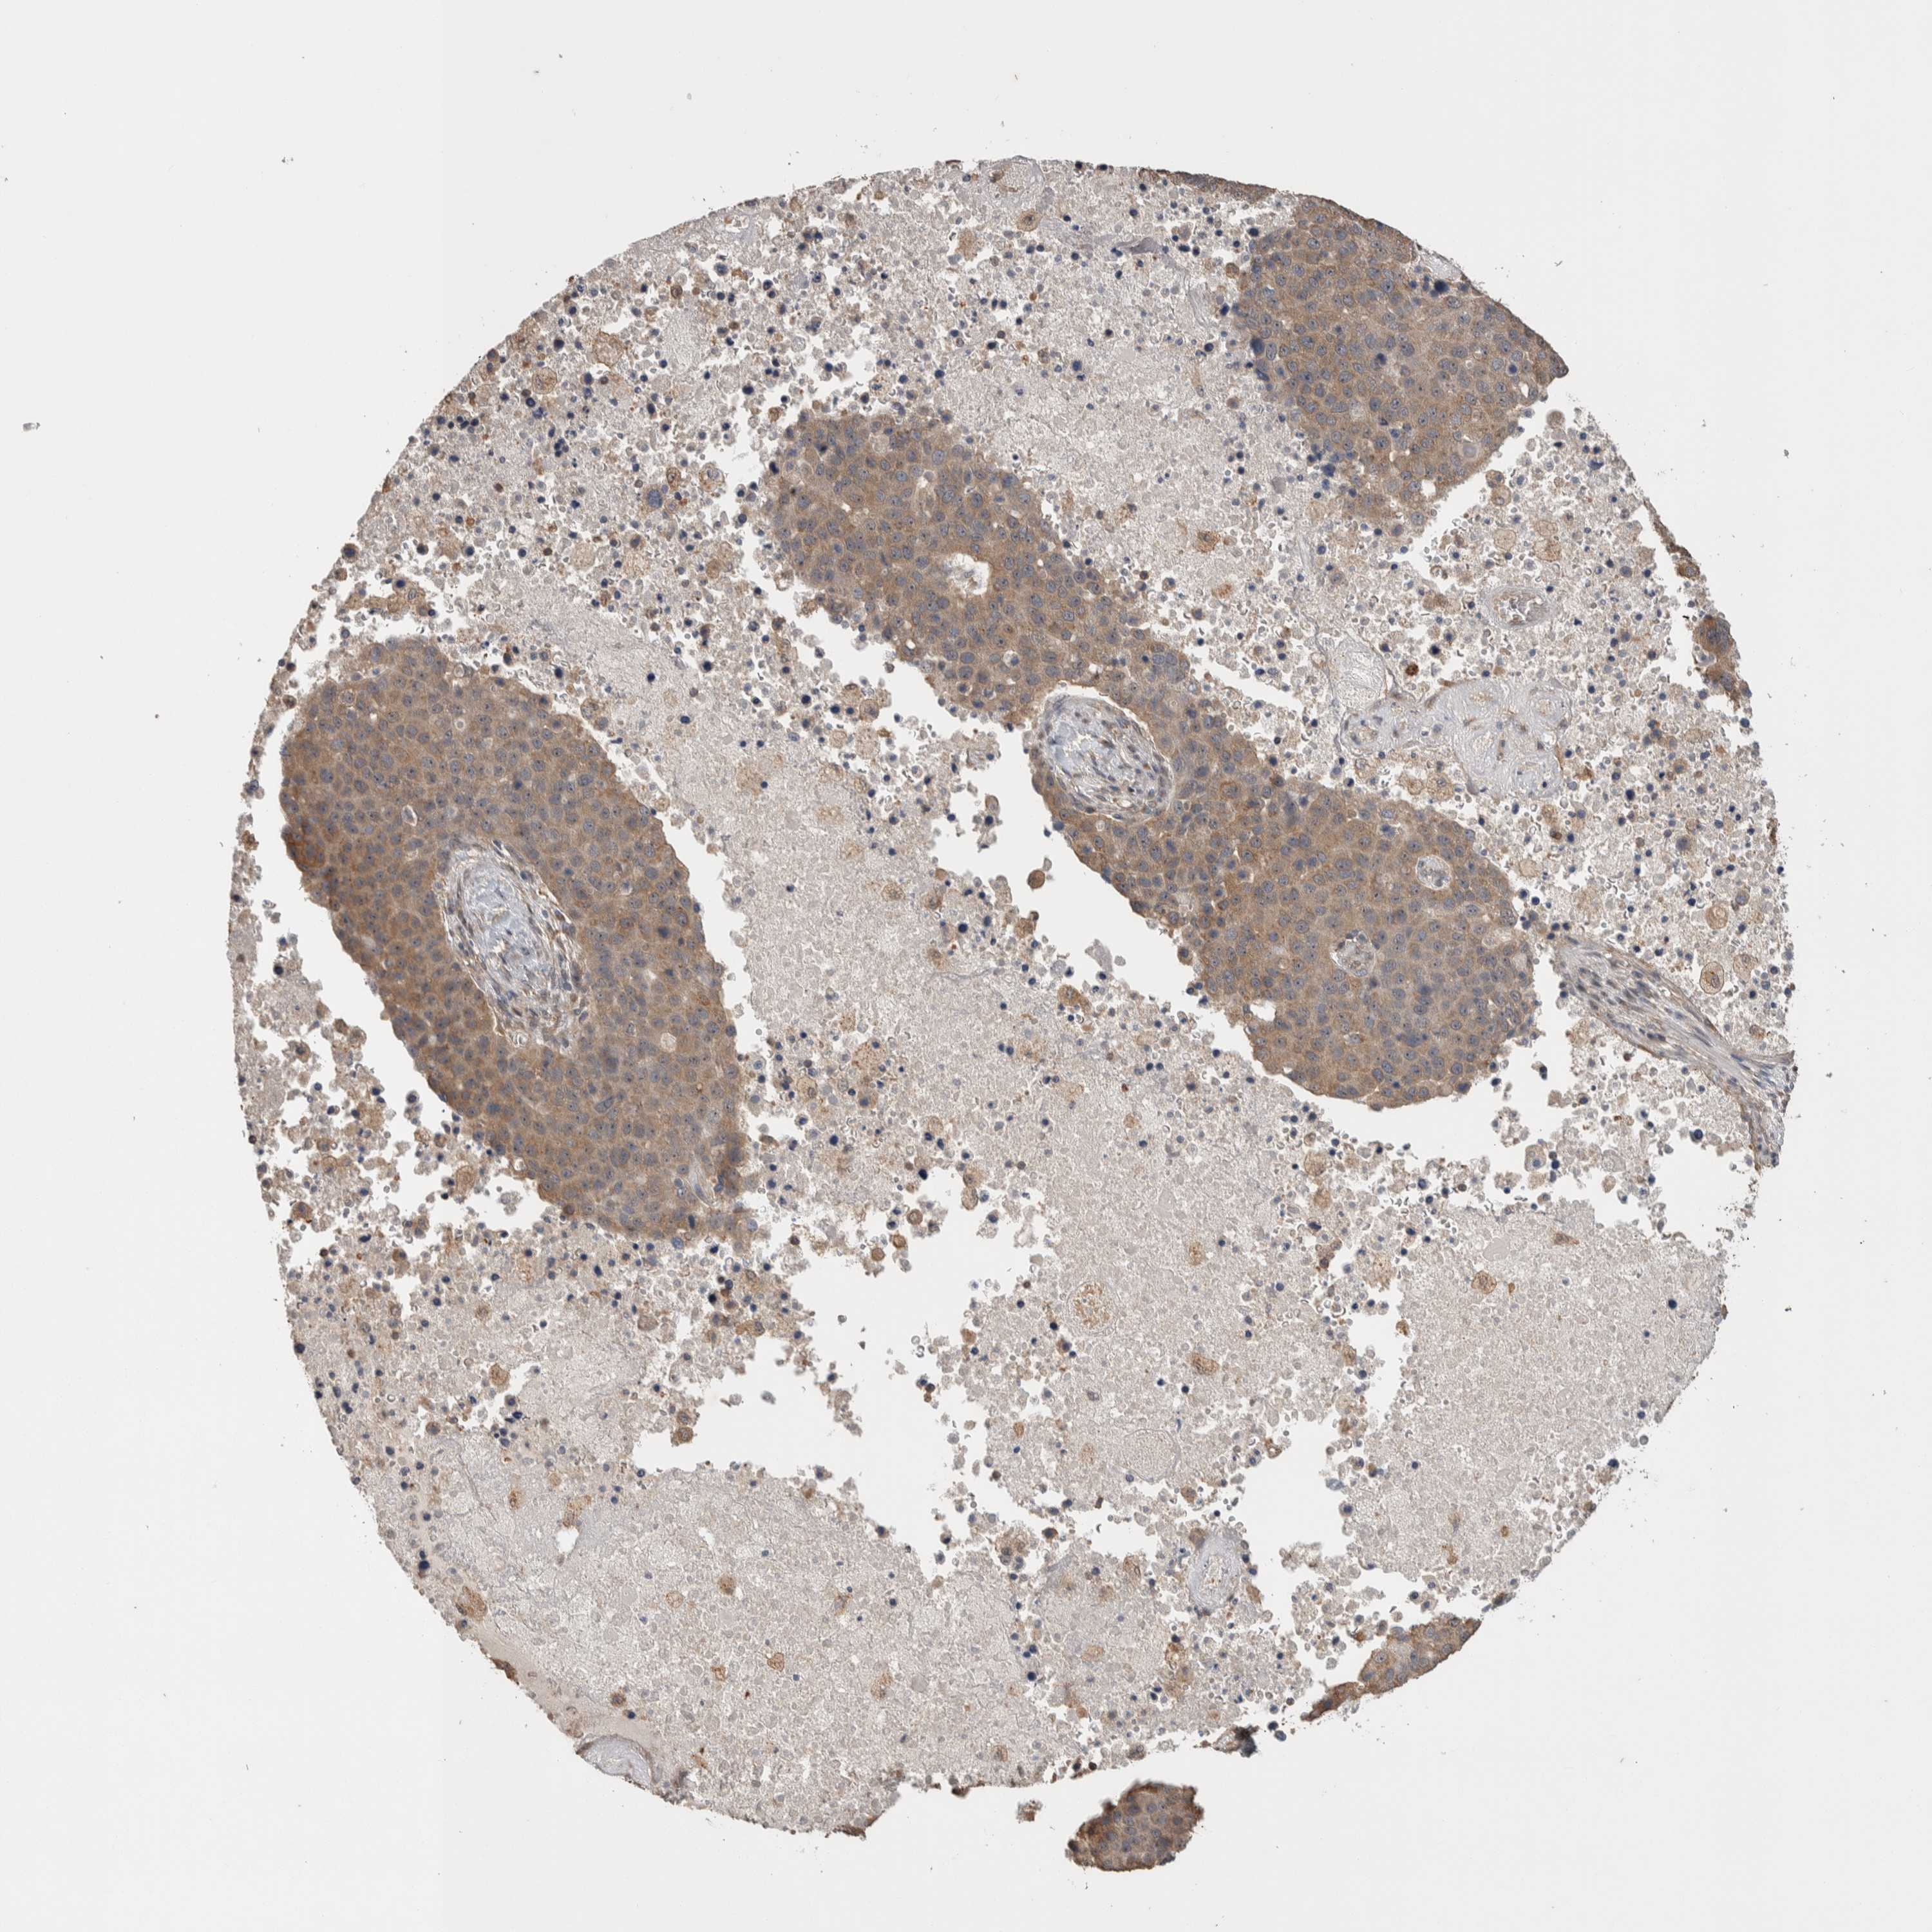

PANCREATIC CANCER - Protein expressioni

A mouse-over function shows sample information and annotation data. Click on an image to view it in a full screen mode. Samples can be filtered based on level of antibody staining by selecting one or several of the following categories: high, medium, low and not detected. The assay and annotation is described here.

Note that samples used for immunohistochemistry by the Human Protein Atlas do not correspond to samples in the TCGA dataset.

Antibody stainingi

Antibody staining in the annotated cell types in the current human tissue is reported as not detected, low, medium, or high, based on conventional immunohistochemistry profiling in selected tissues. This score is based on the combination of the staining intensity and fraction of stained cells.

Each image is clickable and will lead to virtual microscopy that enables deeper exploration of all samples and also displays staining intensity scores, fraction scores and subcellular localization as well as patient and tissue information for each sample.

Antibody HPA022914

Antibody HPA064732

Adenocarcinoma, NOS